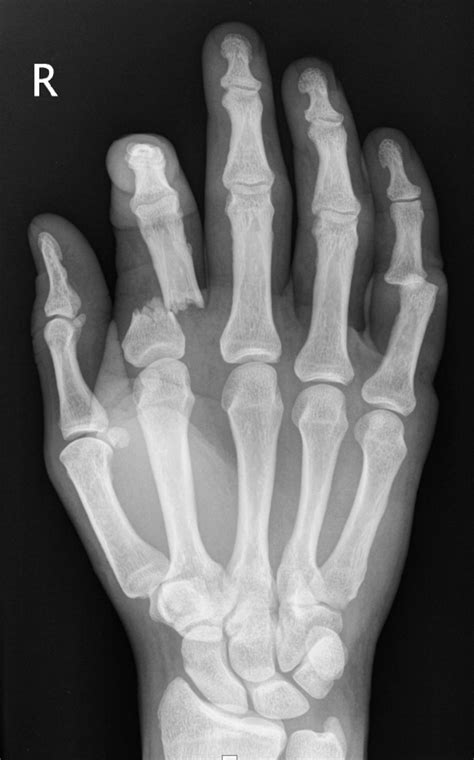

Metacarpal Fractures Fractures in the metacarpal bones, which connect the fingers to the wrist. Punching a hard surface, falls, or direct blows.

Phalangeal Fractures Fractures in the phalanges, which are the bones of the fingers and thumb. Crushing injuries, jamming a finger, or direct trauma.

Boxer's Fracture A specific type of metacarpal fracture, often involving the fourth or fifth metacarpal. Punching a hard object with a closed fist.

Bennett's Fracture A fracture of the base of the first metacarpal bone, often involving the thumb. Falls or direct trauma to the thumb.